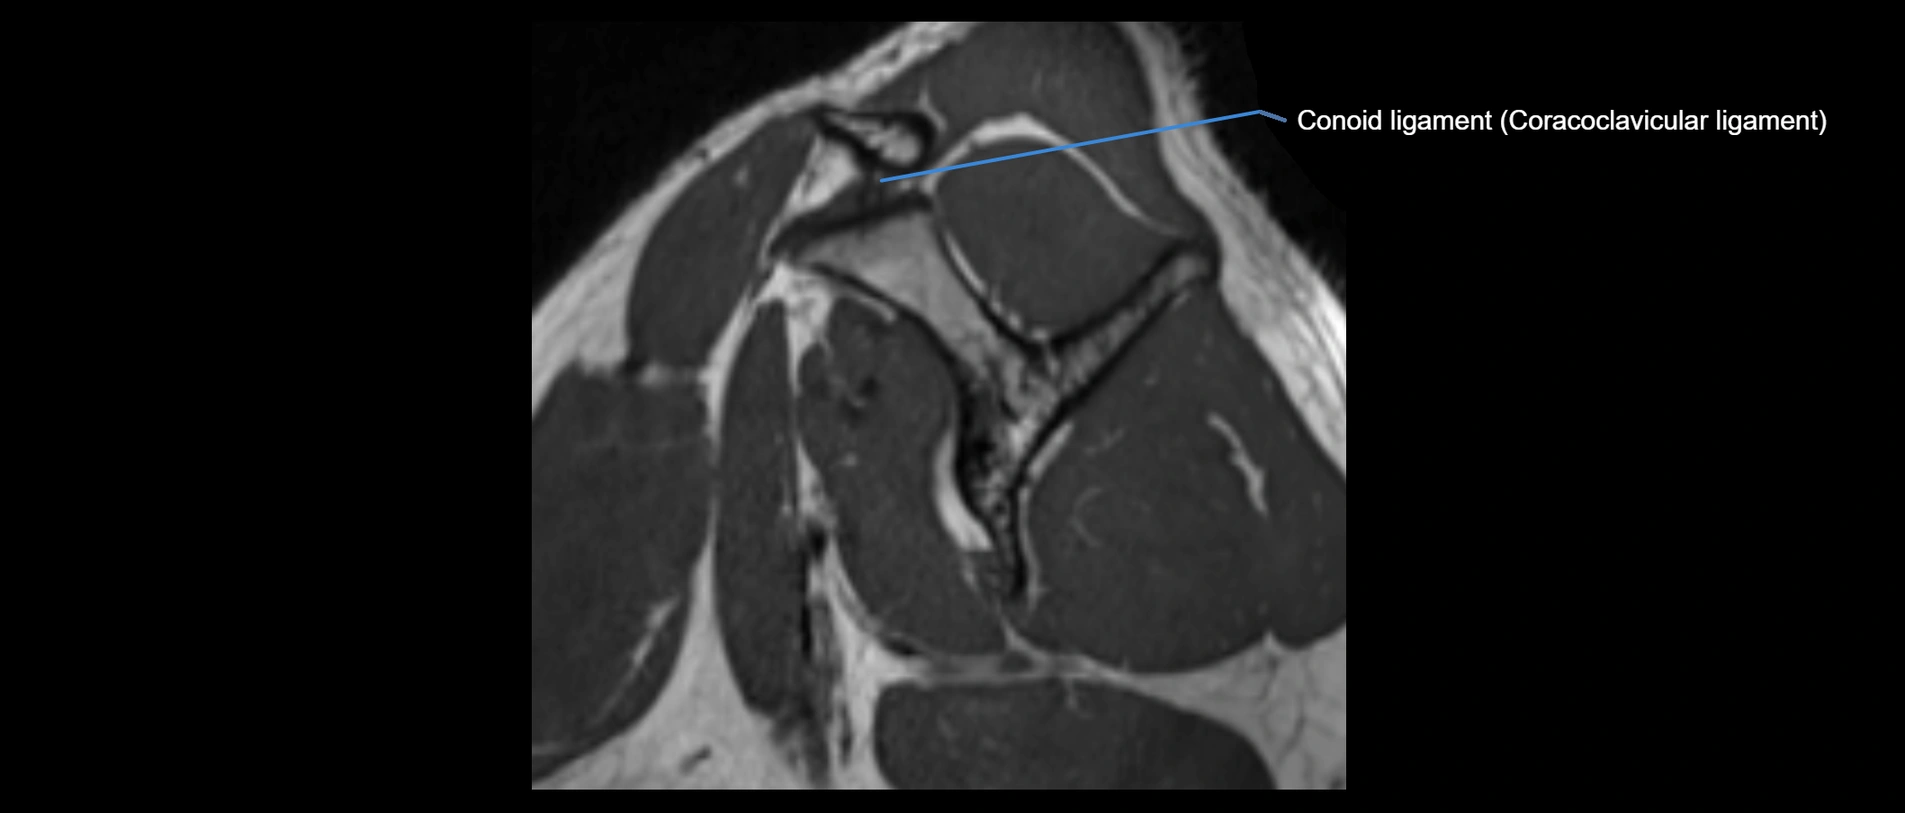

MRI images

image